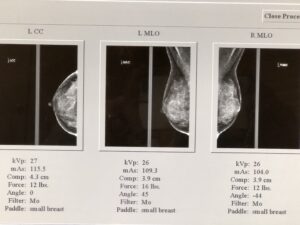

Below are my actual mammogram images from a month before I had my breast augmentation in 2019. My breast tissue is dense (very white) with little fat, so the image does not have much black space.

Your breast will be positioned into position between the plastic plate and paddle, which are then tightened together to flatten and hold your breast tissue still for imaging. During each view (3 images per breast), you are instructed to hold your breath for around 5 seconds as energy is transferred between the plates to visualize your breast tissue. If you have particularly tender breasts around ovulation or menstruation, then you might want to try to schedule your appointment at a time in your cycle when your breasts are not usually sore or take Tylenol or Ibuprofen an hour before your appointment.